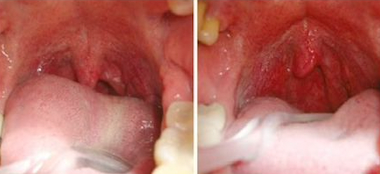

La terapia NightLase de Fotona es un tratamiento láser no invasivo y respetuoso con el paciente que mejora la calidad del sueño del mismo. NightLase reduce los efectos de la apnea del sueño y disminuye la amplitud de los ronquidos gracias al suave tensado producido por la contracción del colágeno en el tejido de la mucosa oral, inducido por láser.

El modo láser Er:YAG patentado por Fotona optimiza la longitud de los pulsos láser, permitiendo la penetración segura del calor en el tejido de la mucosa oral. Es lo suficientemente suave para ser utilizado

en el tejido sensible dentro de la boca, pero lo suficientemente fuerte para proporcionar un calentamiento clínicamente eficaz.